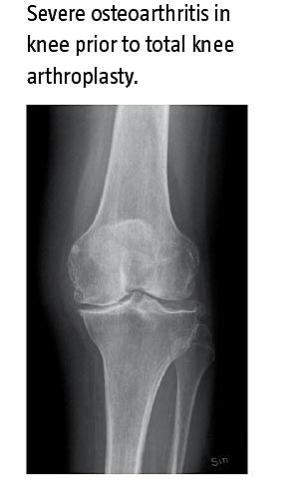

Total knæalloplastik (TKA) har en langtidsvirkende effekt på fysisk funktion og smerter. Dog lider patienterne med TKA efter operation af lavere fysisk funktion end den alders- og kønssvarende baggrundsbefolkning. Genoptræning efter TKA kan i teorien reducere denne forskel, men evidensen er svag. Enkelte studier, der benytter et sent indsættende styrketræningsprogram, viser, at den fysiske funktion forbedres hurtigere med styrketræning end uden styrketræning. Dog er en længerevarende effekt kun fundet i et enkelt studie. Dette studie sammenlignede en gruppe, der deltog i et holdbaseret program med fokus på styrketræning samt uddannelse af patienten, med en gruppe, der modtog superviseret hjemmetræning med de samme træningsøvelser.